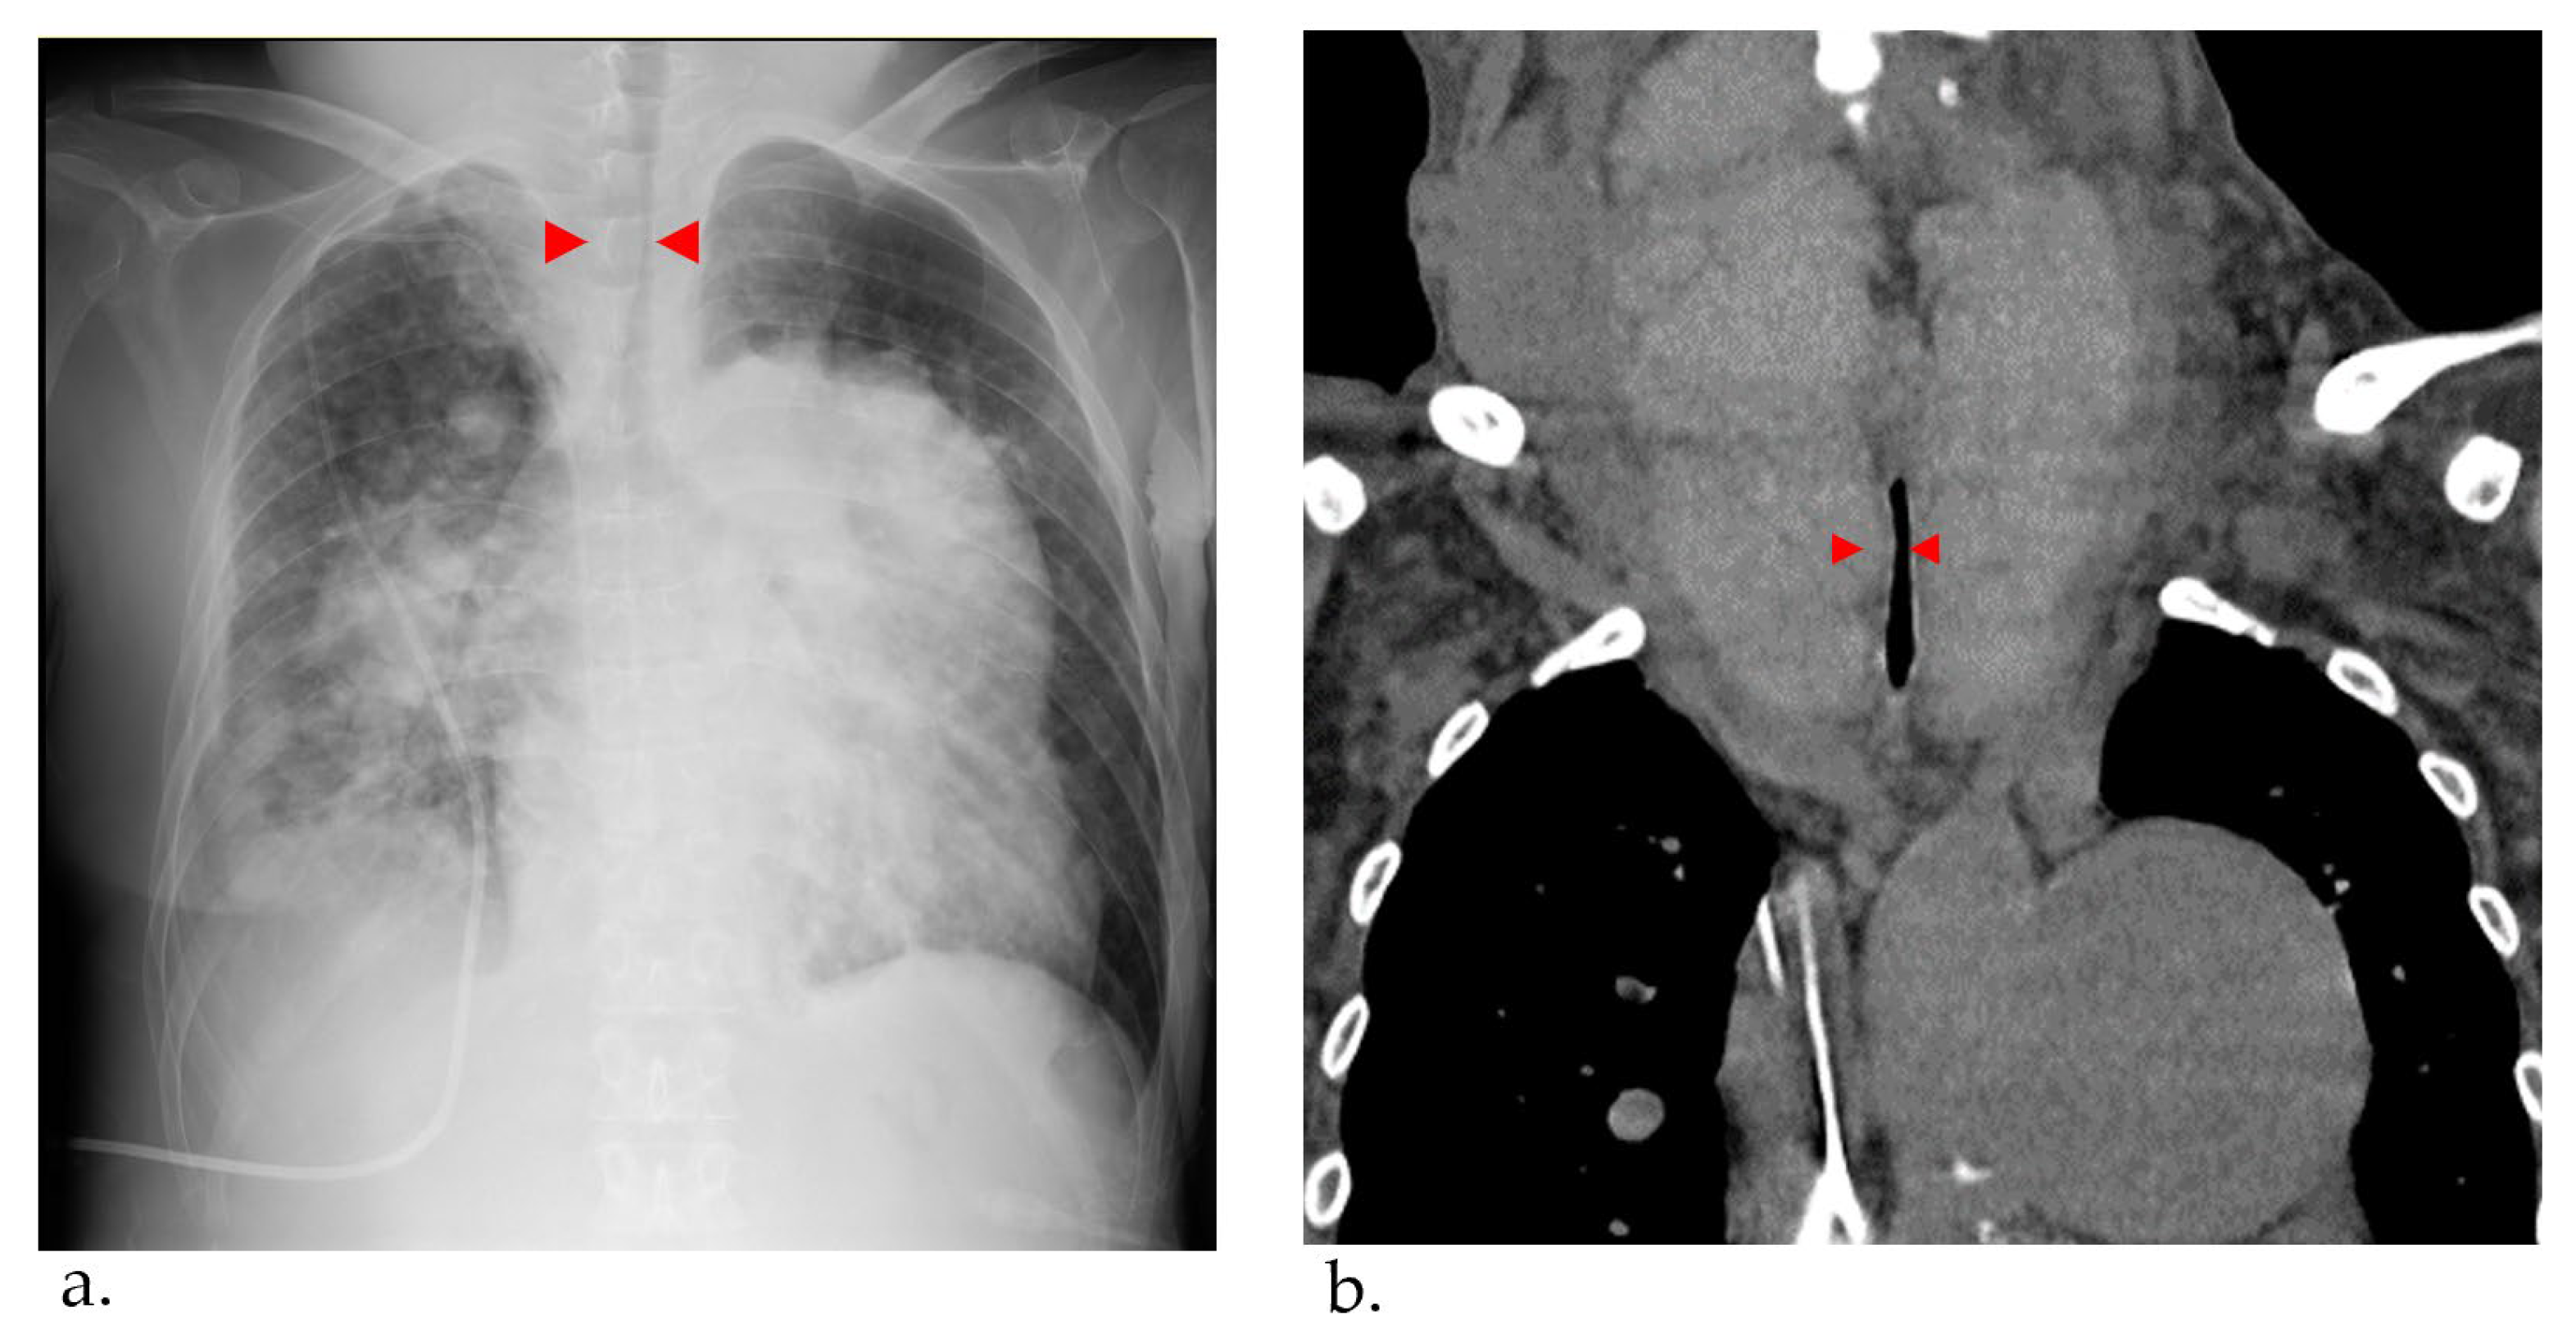

At 56 years of age, she was admitted to the local hospital due to worsening dyspnea. However, cardiogenic shock and respiratory failure with hypercapnia were observed, and she was transferred to our hospital the next day. Upon admission to our hospital, the patient’s vital signs were a blood pressure of 97/62 mmHg, pulse of 117 bpm, and oxygen saturation of 88% with oxygen at 10 L/min through a mask. The dose of epoprostenol at this time was 62.8 ng/kg/min. On examination, the auscultation revealed a diastolic murmur of pulmonary regurgitation and an increased accentuated pulmonary component of the second heart sound in her heart, coarse crackles in her lungs, and stridor in her neck. A chest X-ray revealed bilateral pulmonary congestion and airway stenosis (Figure 3a). Computed tomography of the chest also revealed airway stenosis by her giant goiter (Figure 3b).

Figure 3.

(a) Chest X-ray pulmonary congestion, enlargement of the cardiac shadow, and airway stenosis were detected (red arrowhead). (b) Computed tomography Thyroid gland enlargement was observed. Tracheal compression and stenosis due to goiter (red arrowhead).